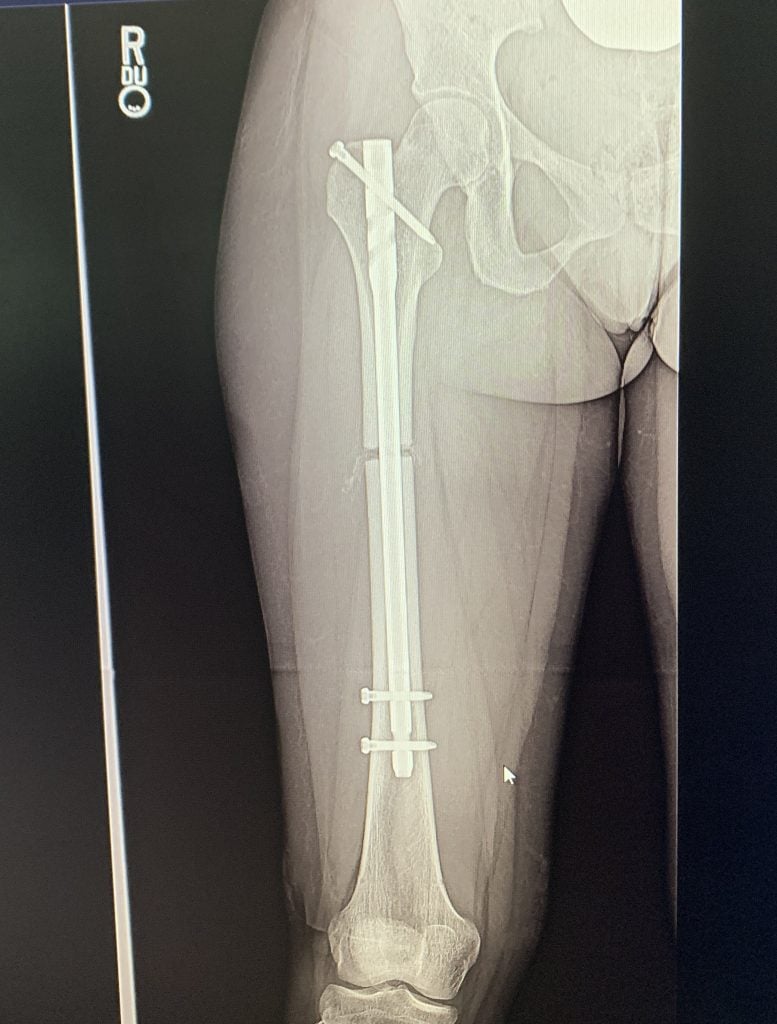

The first doctor I saw told me that I had tendinitis and needed to stop dancing so much, and the next doctor I saw told me that I had a congenital deformity of my femurs, femoral retroversion, that would soon wreck my hips unless I gave up dancing or pursued what sounded like a pretty intense surgery. He referred me to Dr. S. Robert Rozbruch at HSS, and I will forever be thankful that he did!!

Before meeting Dr. Rozbruch, I was terrified that my dancing days were over. Today I am a little over a year post-op femoral osteotomy and hip arthroscopy and feeling fantastic! I am back to dancing full out with no pain or restrictions and have confidence that I will be doing so for a very long time. The surgery I had seems like a scary one, but Dr. Rozbruch's confidence, kindness, and extensive experience made me feel so calm and comfortable throughout the entire experience.